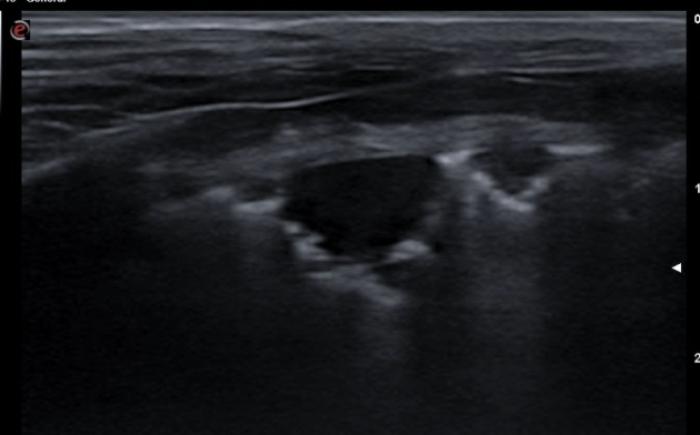

Signo nodular

Consiste en una consolidación de aspecto circular a menudo de anecoicos a hipoecoicos con rara aparición de broncogramas en su interior. Distalmente al signo nodular observamos una línea cóncava hiperecogénica llamada línea C y un refuerzo posterior o signo de brillo en la profundidad del campo. Este hallazgo es común en neoplasias primarias o metastásicas, granulomas fúngicos o abscesos. Es un signo de especial importancia cuando tenemos un paciente con historial oncológico previo o en el protocolo de búsqueda de metástasis. Los nódulos observados veremos cómo se desplazan de izquierda a derecha de la imagen con la respiración del paciente, haciendo patente que se encuentran a nivel pulmonar y no de la pared costal, en cuyo caso no se desplazaran mientras el transductor se encuentre inmóvil (Figura 16A-D).